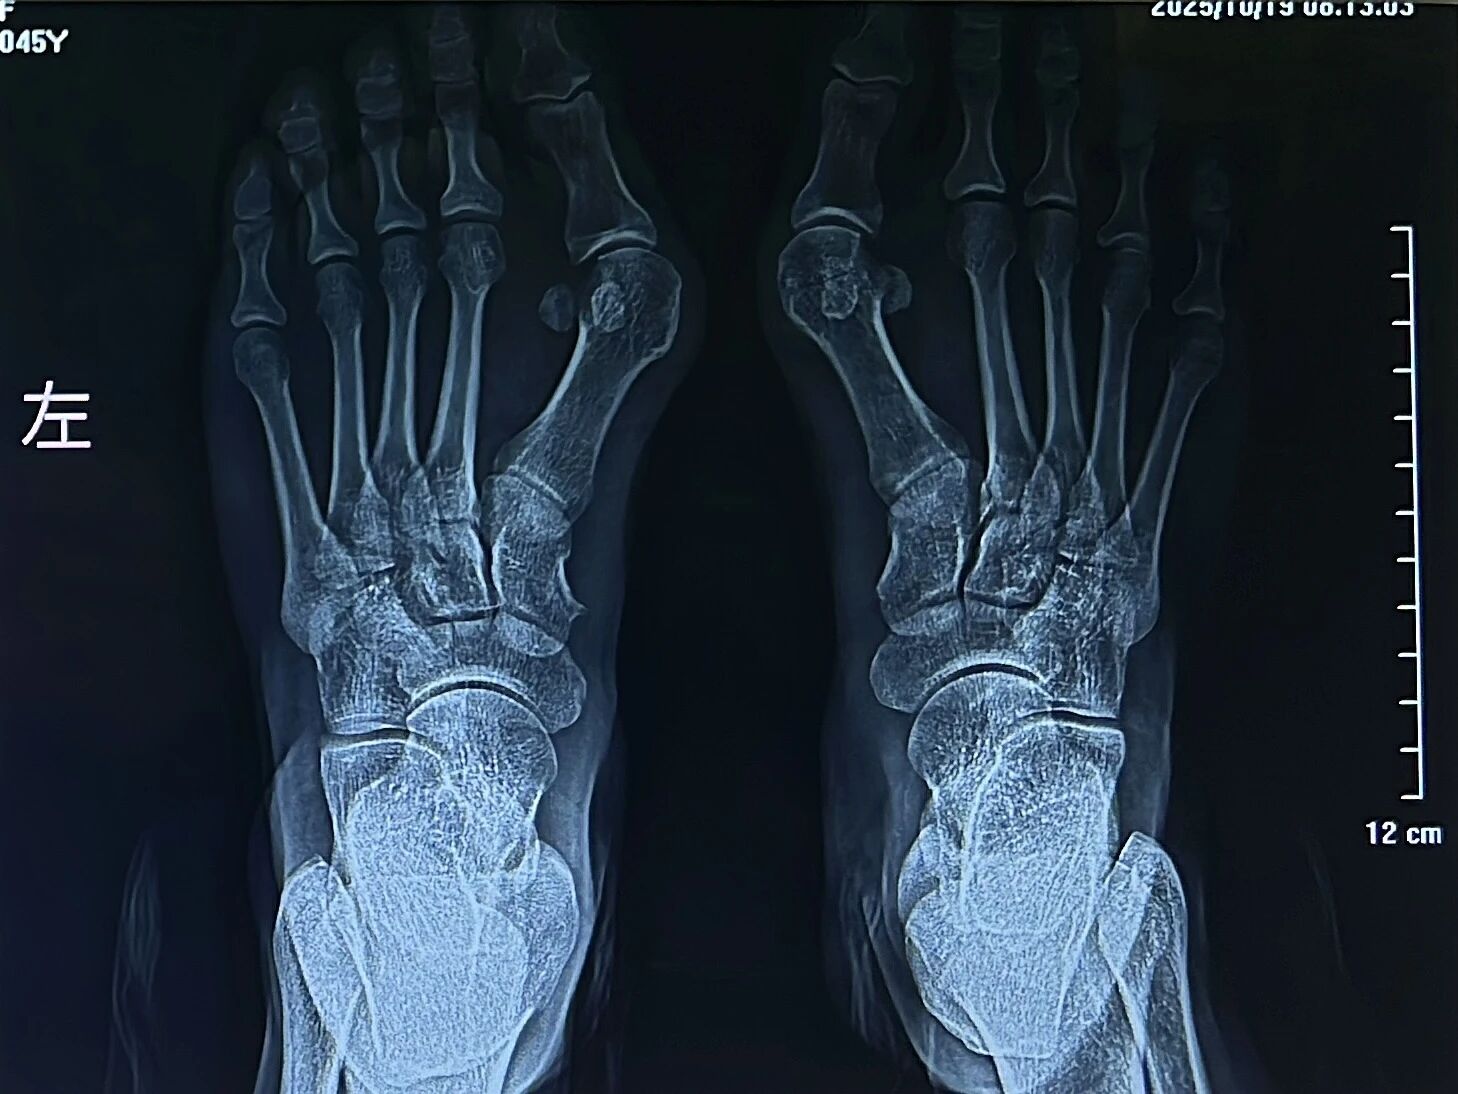

▲术前

▲术后